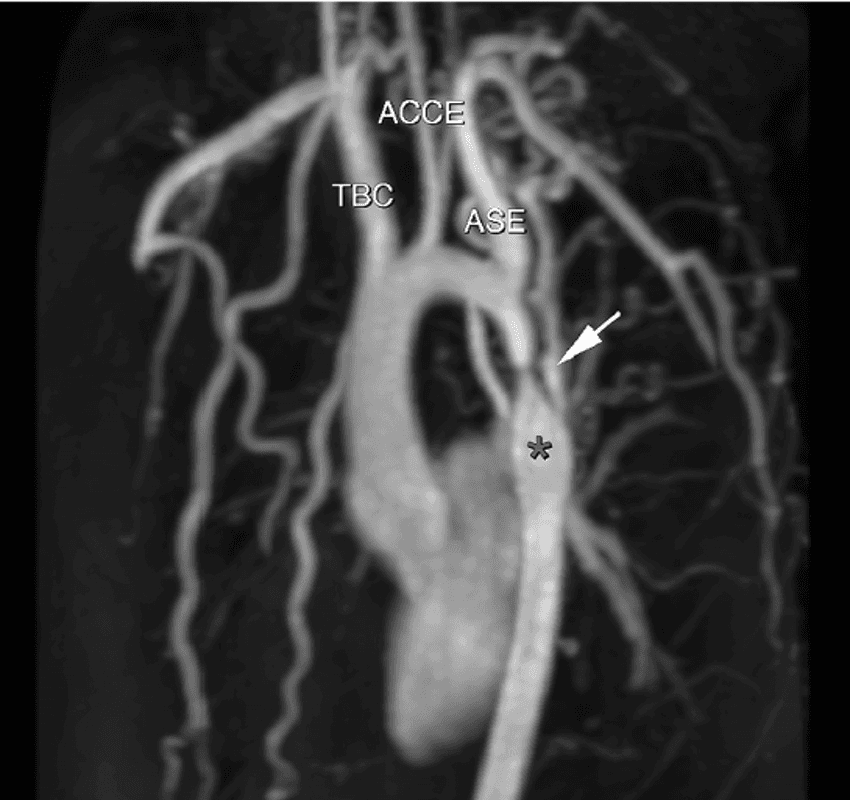

Qué es la Coartación de aorta?Consiste en estrechamiento de la luz del aorta situado la mayoría de las veces ( 96%) en la región localizada entre el origen de la arteria subclavia izquierda y la regió…